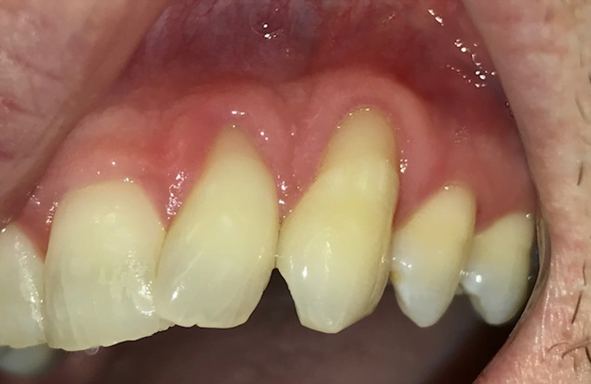

Gum grafting is a dental procedure conducted by Dr. Rivas and his team designed to restore the health and aesthetics of receding gums. Receding gums can cause various dental problems, including tooth sensitivity, tooth loss, and diminished self-confidence.

It involves taking tissue from one area of your mouth (the donor site) and placing it over the affected area (the recipient site). The purpose of this procedure is to strengthen and protect the exposed roots, enhance gum coverage, and improve the overall appearance of your smile.